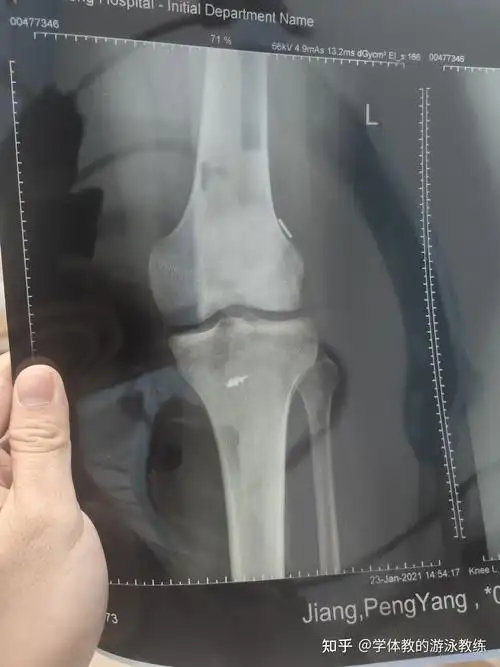

前交叉韧带断裂半月板损伤住院手术过程康复记录